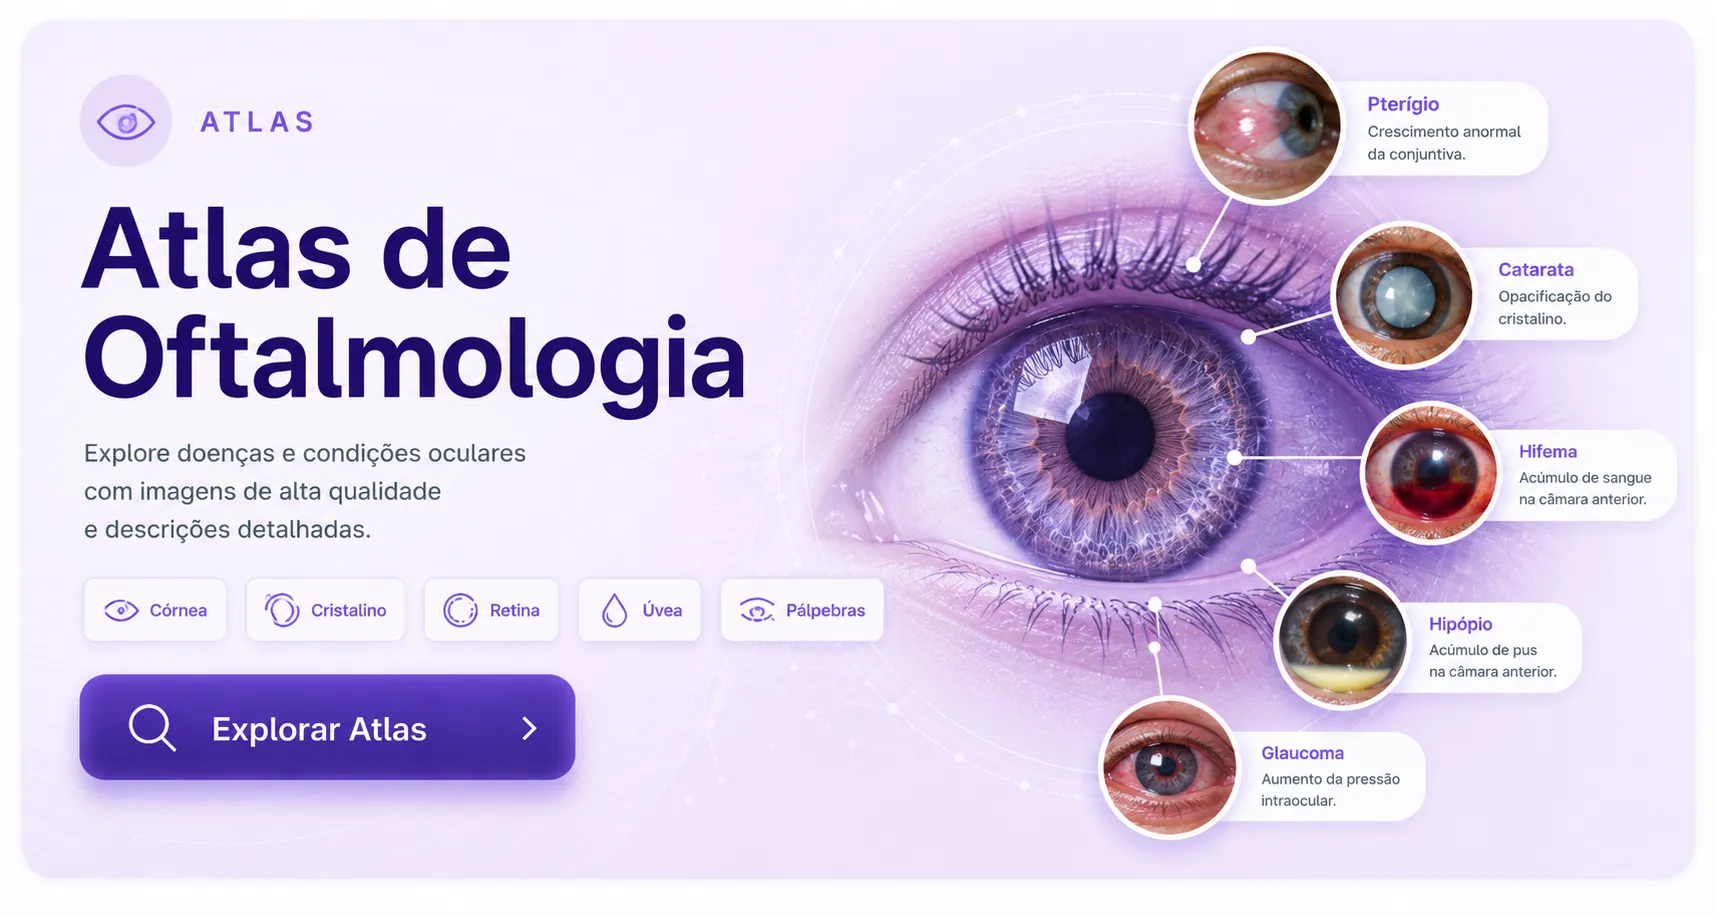

Abrir ferramentaTecnologia visual aplicada ao estudo e à consulta médica.

Explore atlas médicos em alta definição, conteúdos visuais e um guia amplo de zoonoses em uma experiência rápida, organizada e desenvolvida para a prática clínica.

Ler maisAprenda medicina de forma visual.

Explore imagens clínicas e lâminas em alta definição, organizadas para facilitar a identificação de estruturas, doenças e achados importantes no estudo e na prática médica.